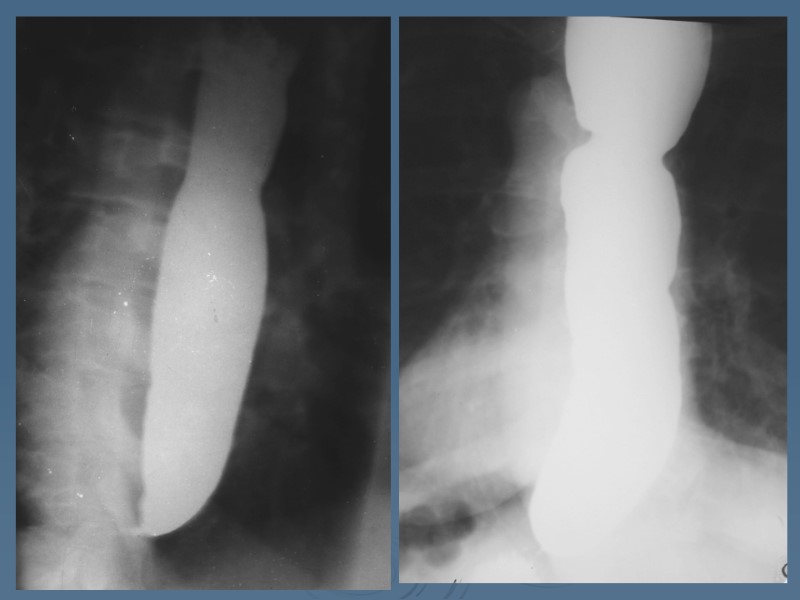

Barium xray of a benign esophageal stricture. Download Scientific Diagram Chest Pain Esophageal Stricture Esophagitis can cause painful, difficult swallowing and chest pain. You may have difficulty swallowing food and liquids, and you may need. The esophagus is a tube that. Many different things can cause esophagitis. With this condition, the esophagus contracts asynchronously, leading to uneven peristalsis. Esophageal spasms can feel like sudden, severe chest pain that lasts from a few minutes to. Chest Pain Esophageal Stricture.

Segmental esophageal strictures. a, b Oblique single contrast views of... Download Scientific Chest Pain Esophageal Stricture With this condition, the esophagus contracts asynchronously, leading to uneven peristalsis. Some people may mistake it. You may have difficulty swallowing food and liquids, and you may need. Esophagitis can cause painful, difficult swallowing and chest pain. The main symptom of an esophageal stricture is dysphagia, meaning difficulty in swallowing. This may manifest as a sensation of food sticking or. Chest Pain Esophageal Stricture.

Esophagram findings; the esophagram shows stricture in the middle... Download Scientific Diagram Chest Pain Esophageal Stricture Esophageal dysphagia refers to the sensation of food sticking or getting caught in the base of the throat or in the chest after. Esophagitis can cause painful, difficult swallowing and chest pain. With this condition, the esophagus contracts asynchronously, leading to uneven peristalsis. The main symptom of an esophageal stricture is dysphagia, meaning difficulty in swallowing. This may manifest as. Chest Pain Esophageal Stricture.